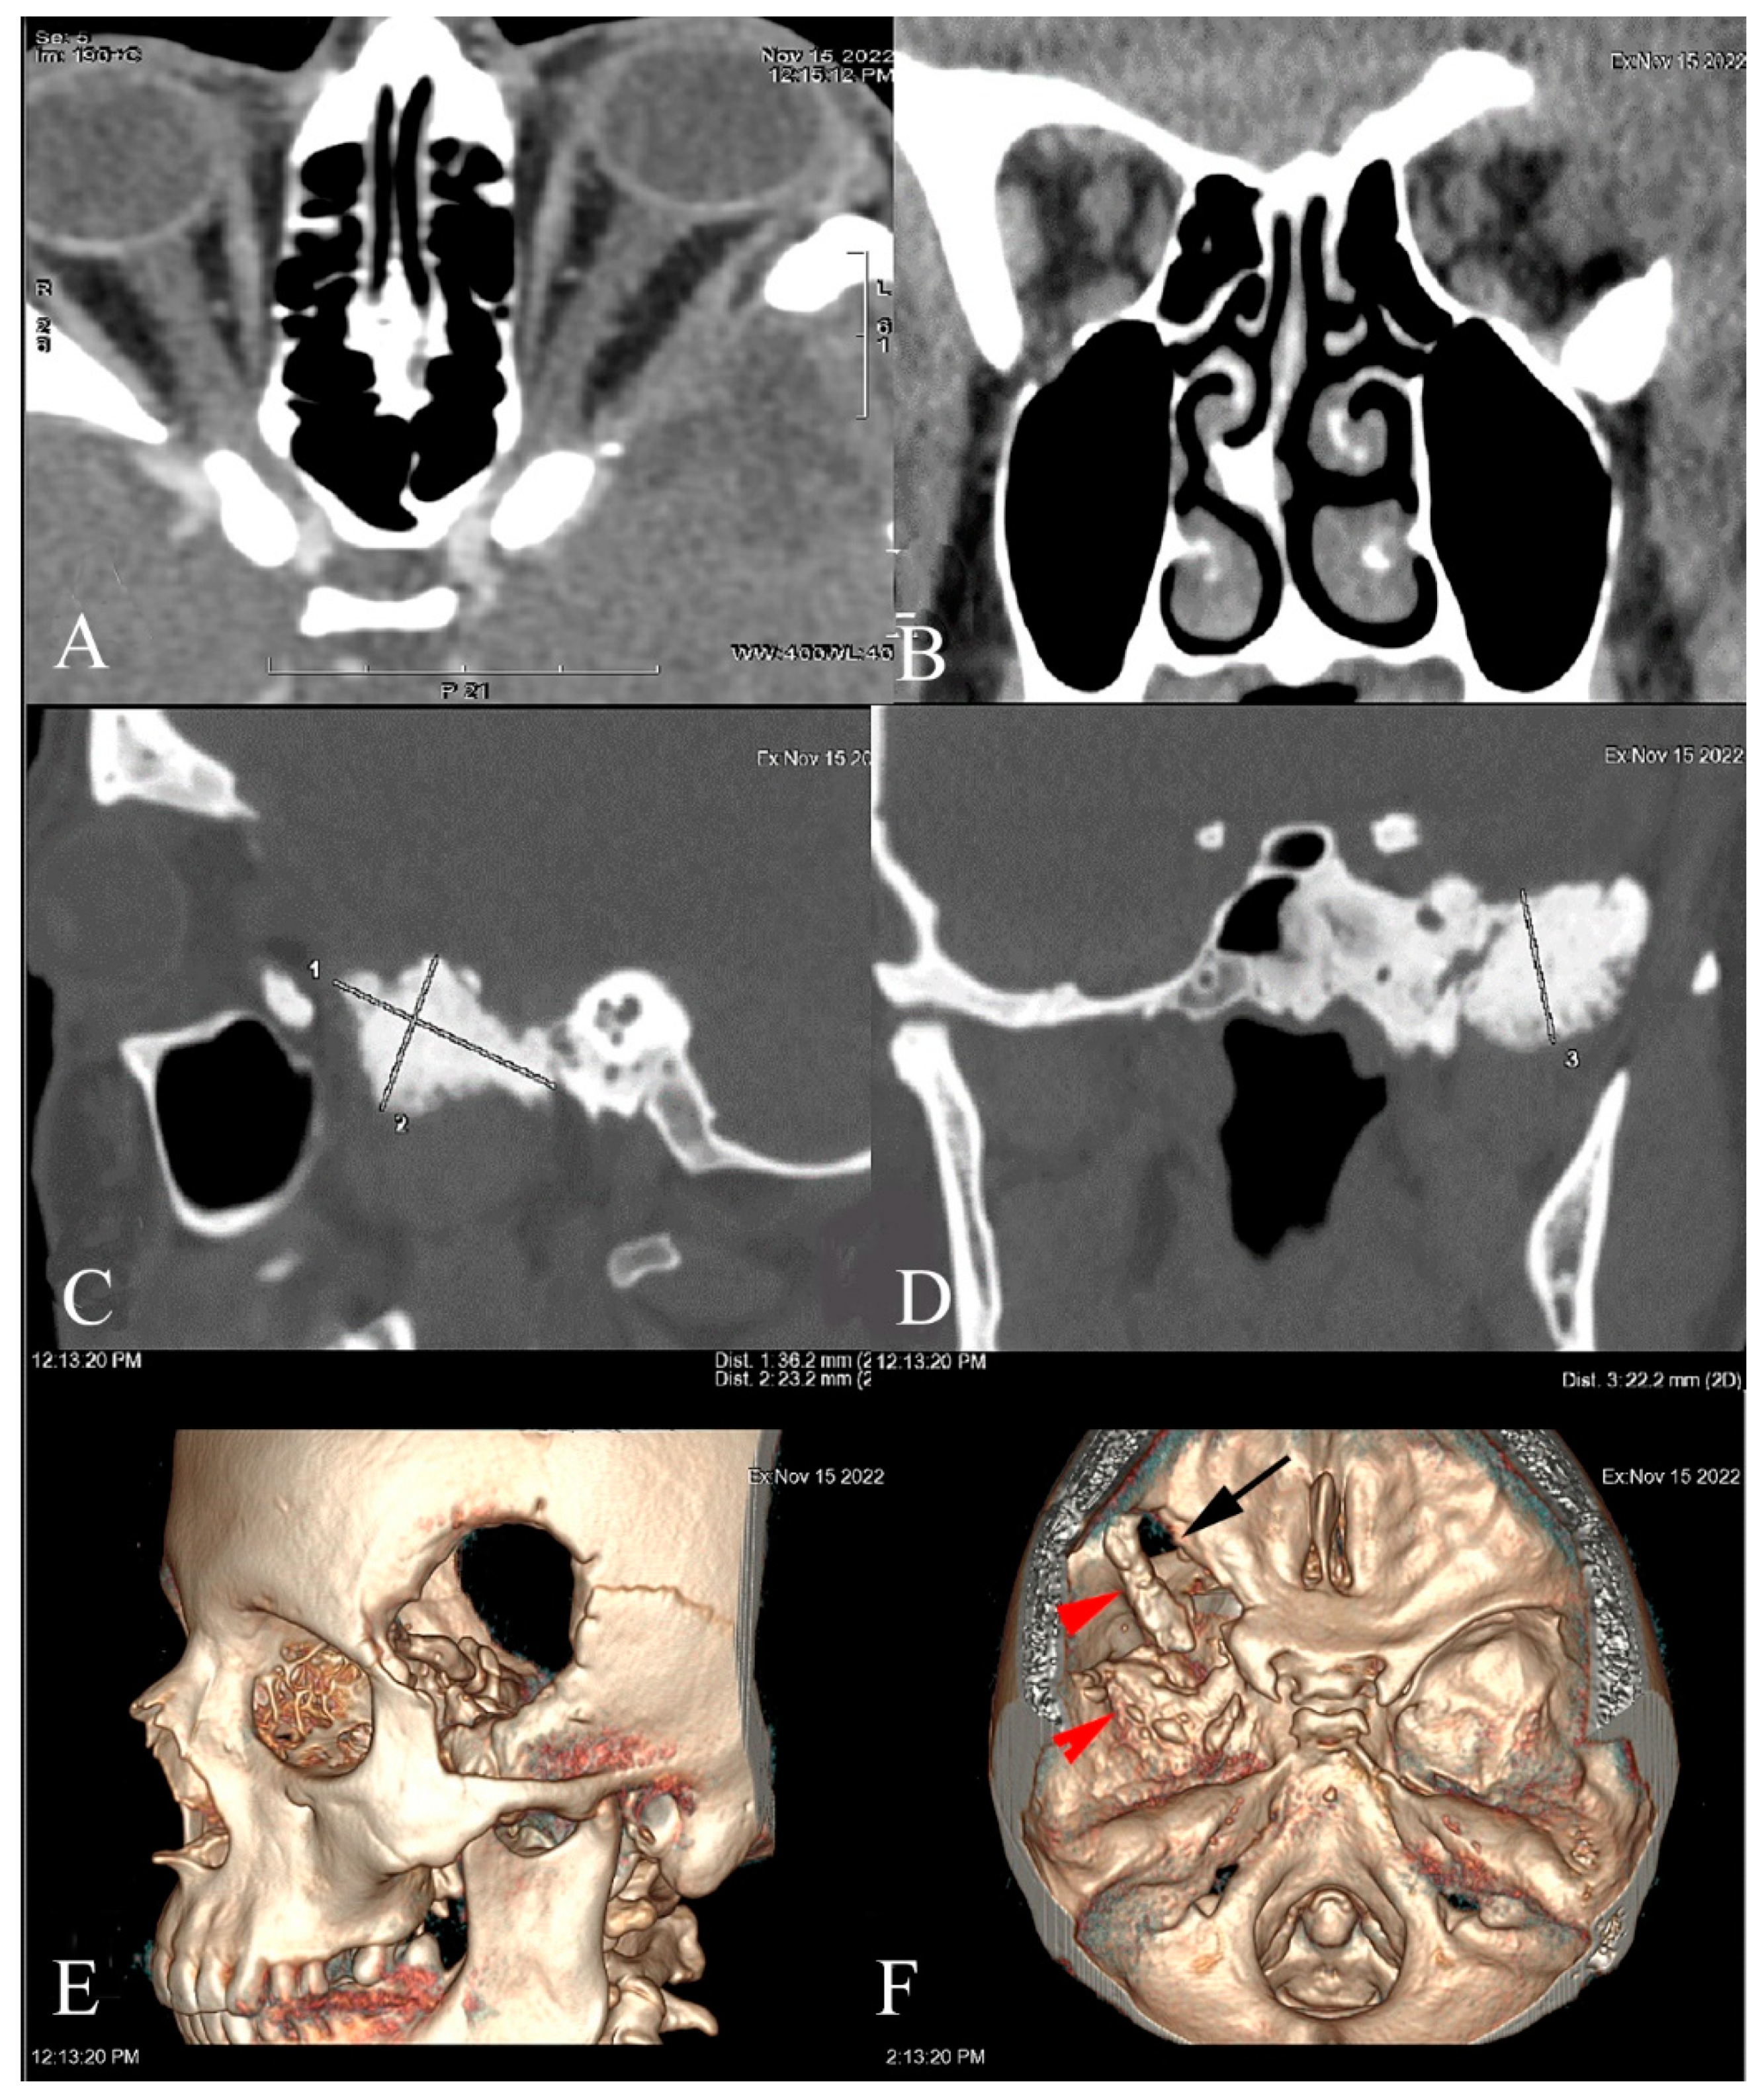

2. Case Report